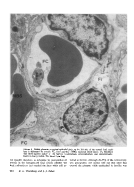

Ferritin was injected into the fetal or the maternal circulation of 27-29-day-pregnant rabbits. After the occurrence of a quasi-steady state, the placentas were prepared for electron microscopy. Ferritin particles were counted in the electron micrographs in the fetal capillaries, in the maternal blood spaces, and in the two interstitial compartments of the three-layered placenta. Under the circumstances of the experiments (excessively elevated plasma ferritin concentrations), no evidence was found for nondiffusional transport of radiolabeled ferritin. Comparison of the standing concentration gradients in the placentas, recorded after maternal and after fetal injection, showed that the interstitial spaces "excluded" ferritin; the plasma-interstitial space ferritin partition coefficients were 10 in the basement membrane space and 3 in the space between the cyto- and syncytiotrophoblasts. 55% of the total concentration gradient across the rabbit placenta occurred across the fetal endothelium, about 45% across the cytotrophoblast, and less than 5% across the syncytiotrophoblast. These figures are believed to reflect the relative contributions of these three layers to the total diffusional resistance in the rabbit placenta. When compared to previous data on the relative contributions of these three layers for small ions and molecules, the present data lead to the conclusion that discrimination of molecular size is a function of the fetal capillary endothelium alone.